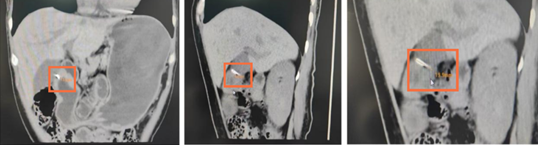

CT发现体内金属异物

这次,谜底终于露出了蛛丝马迹。影像显示,她的胃壁内可见一个细长的条状高密度影。这个影子非常隐蔽,在普通检查中很容易被忽略。结合她最初咽喉刺痛的经历,医生们判断:这很可能是一个被胃壁完全包裹的异物。就像“潜水艇”潜入了深海,它藏在胃壁肌肉里,导致多次胃镜观察胃内表面都“风平浪静”,无法发现。